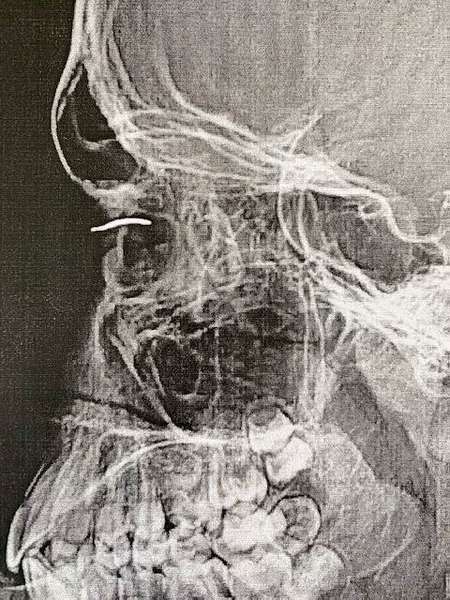

У луцькому перинатальному рятували хлопчика, якому шматок дроту потрапив в око.

Про це розповіли у Волинському обласному перинатальному центрі.

На фото пацієнт з проникаючим пораненням ока та стороннім тілом (дріт з батога).

«Вдома робили невдалу спробу самостійно витягнути дріт. У відділенні офтальмології з центром хірургії ока Волинської обласної дитячої клінічної лікарні хлопчик успішно прооперований. Зір відновлено до 100%», – зазначили лікарі.